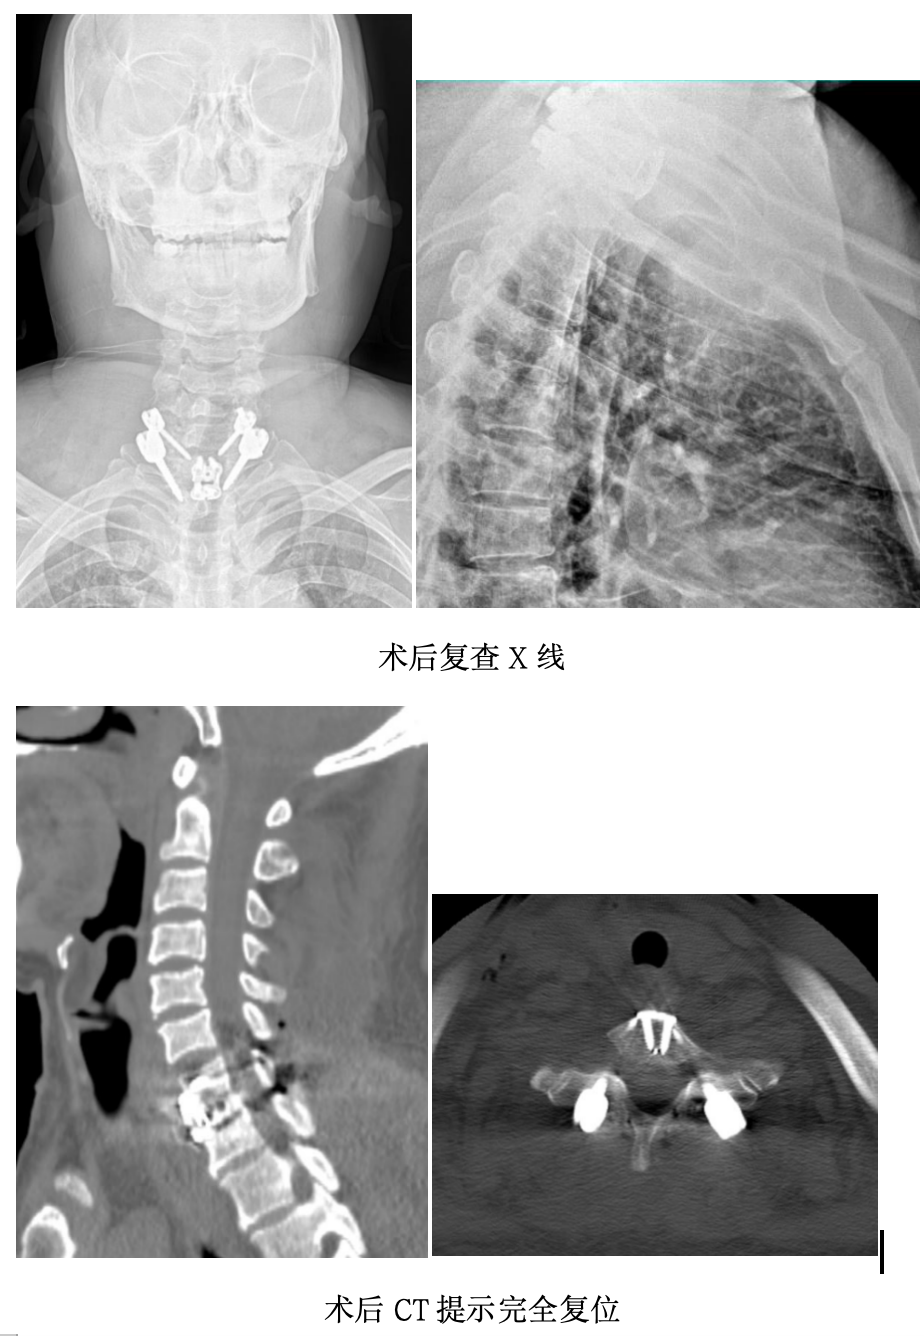

关键时刻,团队当机立断,调整策略。主刀医生决定采用“前-后-前”联合入路:先将患者翻身至俯卧位,经后路切口暴露脱位节段,植入椎弓根螺钉,借助连接棒的杠杆力量进行提拉复位。随后,患者再次被翻回仰卧位,术者经前路探查确认——之前明显的“阶梯感”消失了,脱位已成功复位,随即完成前路固定。

这场“前-后-前”联合入路手术,历时5小时,两次术中翻身,不仅是对技术的考验,更是对团队协作与应急决策的极致挑战。

手术成功只是第一步。术后患者清醒后,四肢活动自如。复查影像显示:脱位已完全矫正,内固定位置完美,脊髓形态正常。